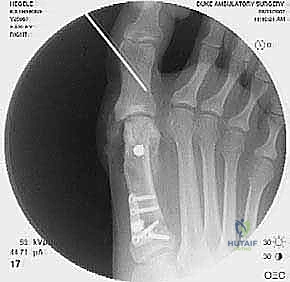

2. التصوير الشعاعي المتقدم

- الأشعة السينية مع تحمل الوزن (Weight-bearing X-rays): صور من الأمام، الجانب، والزوايا المائلة لتقييم زوايا العظام تحت تأثير وزن الجسم.

- تصوير السمسمانيات (Sesamoid view): لمعرفة ما إذا كانت العظام السمسمانية قد خُلعت من مكانها.

- الأشعة المقطعية (CT Scan): في الحالات المعقدة، يستخدم الدكتور هطيف الأشعة المقطعية ثلاثية الأبعاد لتقييم التئام العظام السابق، ومواقع المسامير القديمة، ودرجة خشونة المفاصل بدقة متناهية.

جراحة المراجعة هي عمل فني وهندسي معقد. إليك كيف يقوم الأستاذ الدكتور محمد هطيف بإجرائها خطوة بخطوة، معتمدًا على أحدث التقنيات العالمية:

- يتم تحديد مواقع المسامير أو الشرائح المعدنية من الجراحة السابقة وإزالتها (Hardware Removal). قد تكون هذه الخطوة صعبة إذا نما العظم فوق المسامير.

ب. عملية لابيدوس (Lapidus Procedure - TMTJ Arthrodesis)

إذا كان سبب التكرار هو "فرط الحركة" في مفصل منتصف القدم (TMTJ)، فإن الحل الوحيد لمنع التكرار المستقبلي هو دمج (إيثاق) هذا المفصل. يزيل الدكتور هطيف الغضروف من المفصل، يصحح زاوية العظم، ويثبته بشريحة معدنية قوية ومسامير حتى يلتحم العظمان معًا. هذه العملية تعالج أصل المشكلة من الجذور.

ج. إيثاق مفصل المشط السلامي الأول (First MTPJ Arthrodesis)

يُعتبر هذا الإجراء "المعيار الذهبي" (Gold Standard) وجراحة الإنقاذ النهائية في حالات المراجعة المعقدة، خاصة إذا كان المريض يعاني من:

* تدمير المفصل أو خشونة شديدة (التهاب المفاصل العظمي).

* فقدان عظمي كبير من الجراحة السابقة.

* تكرار شديد للتشوه مصحوب بألم مبرح.

في هذه العملية، يتم إزالة الغضروف التالف من مفصل الإصبع الكبير، ودمج العظام معًا في وضع مستقيم قليلاً للأعلى للسماح بالمشي الطبيعي. يتم التثبيت باستخدام شريحة ومسامير متقاطعة. النتيجة هي إصبع مستقيم، خالٍ تمامًا من الألم، ولا يمكن أن يعود للتشوه أبدًا.